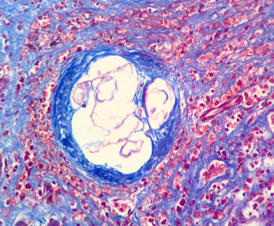

Microscopic (histologic) description

- Ova are mainly seen in the loose submucosa of large intestine, usually with formation of granulomas and infiltration by eosinophils and inflammatory cells

- Later the muscularis mucosa becomes involved and the overlying mucosa shows small superficial ulcers

- Fibrosis develops in chronic stage, when only calcified eggs are seen

Microscopic (histologic) images

Contributed by Nalini Bansal Gupta, M.D., Lisa Cerilli, M.D. and @zaalruwai83 on Twitter